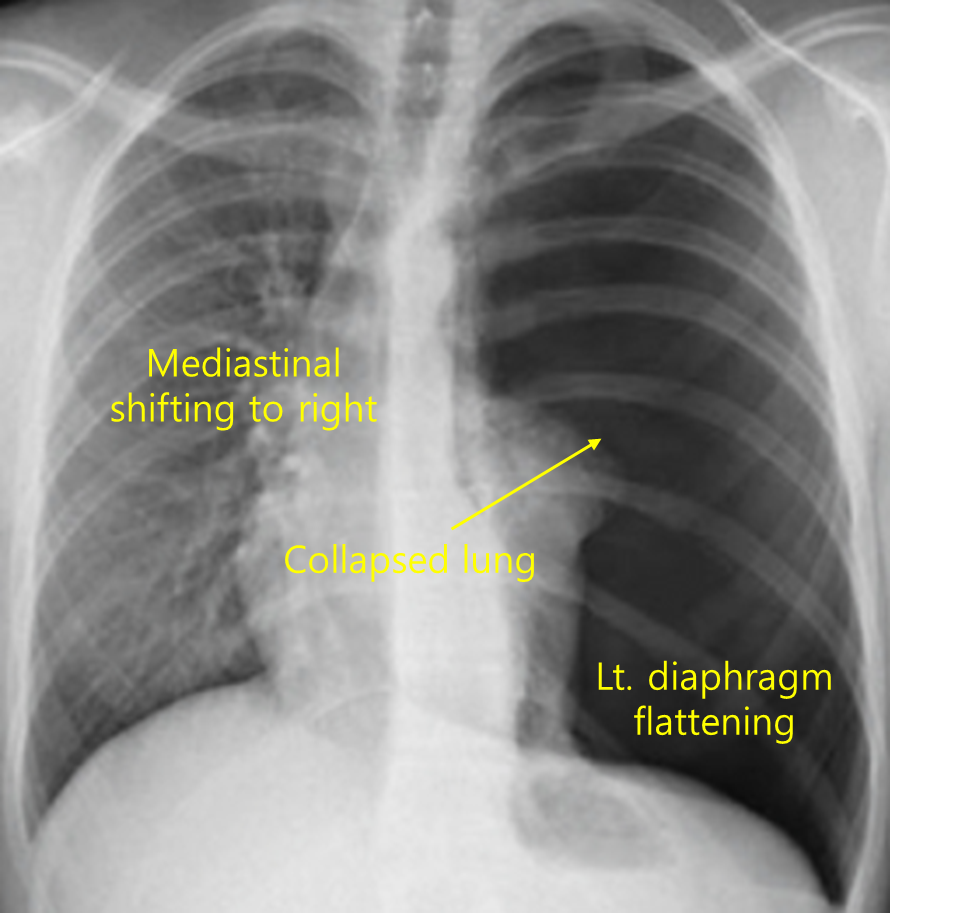

34세 남자가 1시간 전부터 왼쪽 가슴이 아프다며 병원에 왔다. 3년 전부터 흡연을 해왔다고 한다. 혈압 80/50mmHg, 맥박 120회/분, 호흡 35회/분, 체온 37℃, 산소포화도 95%이다. 왼쪽 가슴에서 호흡음이 감소되고 타진에서 가스팽만음이 들린다. 가슴 X선 사진이다. 혈압을 올리기 위한 조치는?

Img | CXR: 좌측 폐 bronchovascular marking 사라짐, 심장 및 기도 우측 이동 |

Imp: 긴장성 기흉(tension pneumothorax)

V/S이 unstable하고 large mediastinal shift가 관찰되므로 긴장성 기흉 진단 하, 굵은 바늘 삽입을 시행한다.

• CXR에서 좌측 폐의 폐혈관 음영이 완전히 사라졌고, 심장과 기도가 우측으로 이동한 소견이 보이며, 저혈압이 저명하므로 긴장성 기흉이 의심된다.

• 긴장성 기흉에서 우선되는 처치는 흉막 천자를 통한 감압이다.

긴장성 기흉 | • V/S unstable • CXR: Mediastinal shift • 즉각적인 바늘 감압 → 이후 흉관 삽입 |